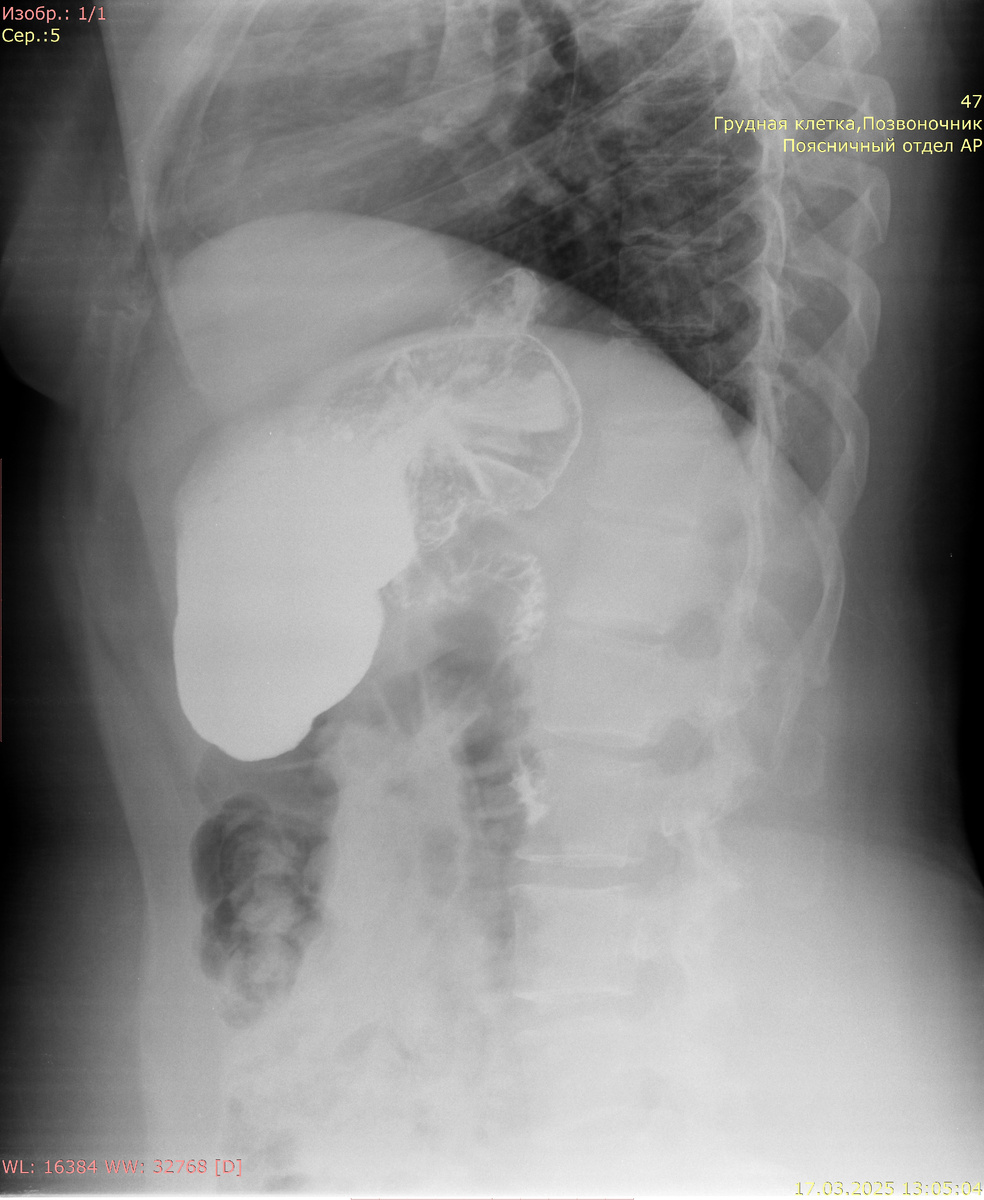

Рентгенография желудка с сульфатом Ва:

Кардиальный жом функционирует. Желудок не деформирован, объем обычный, смещаемость не нарушена. Контуры желудка ровные, отвесные, участков деформации не выявлено. Рельеф слизистой не изменен, складки не утолщены. Контраст своевременно поступает в ДПК. В положении лежа при натуживании определяется пролабирование кардиальных складок выше диафрагмы размерами 66 мм х 61 мм.

Заключение: Скользящая грыжа пищеводного отверстия диафрагмы 3-4 ст.